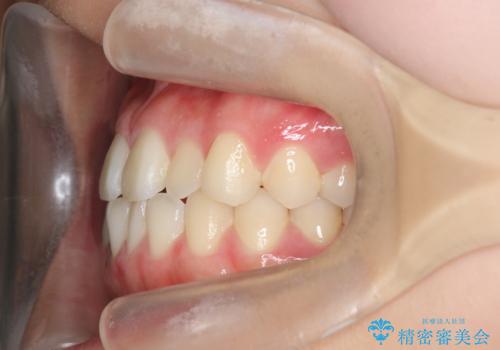

ガタつきの改善 マウスピース矯正治療

- 歯のがたつきの改善を求めて、矯正治療を希望され来院されました。

少量の歯のディスキング、歯列弓拡大、アタッチメントを装着することで審美的な歯列へとマウスピース矯正インビザラインを用いて治療を行います。

マウスピース矯正は装着時間の遵守が非常に大切ですが、しっかりと20時間/日以上の装着を守っていただいたおかげで良好な治療結果を得ることができました。